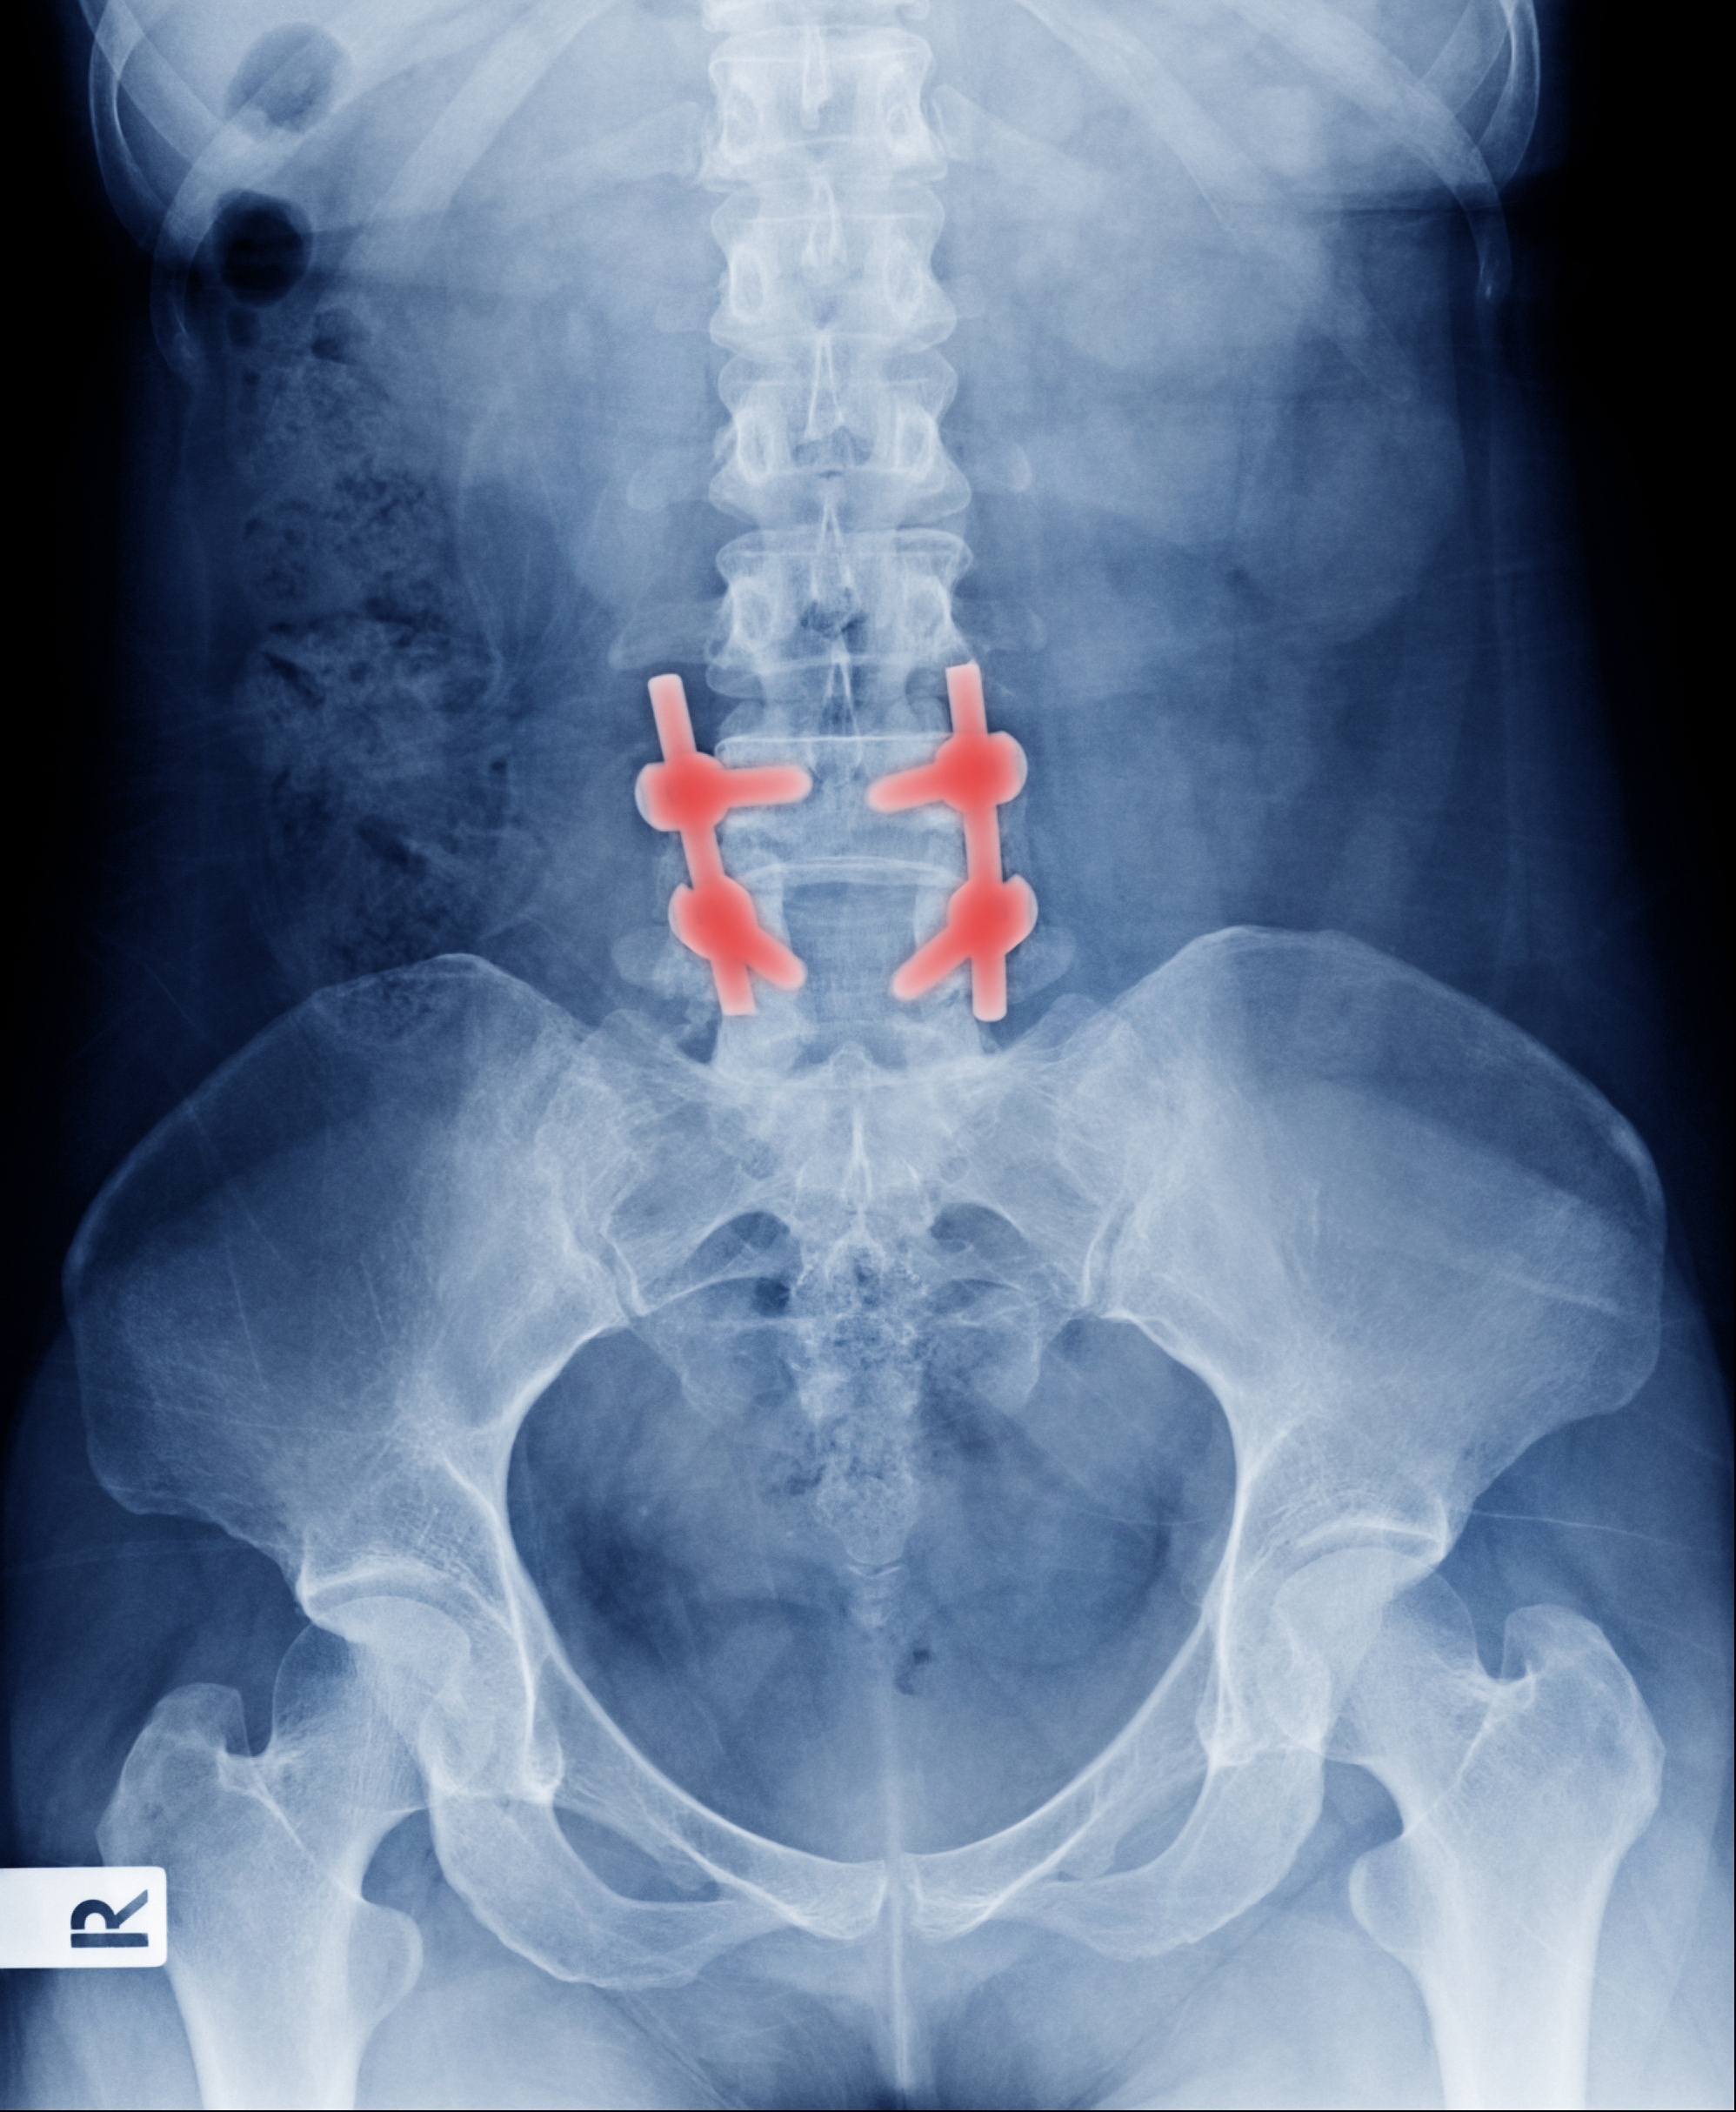

At Total Spine & Orthopedics, we offer an alternative to traditional open-back fusion. Our minimally invasive transforaminal lumbar interbody fusion (TLIF) provides a less invasive solution for your chronic lumbar pain. During our procedure, your surrounding muscles and tissue are not disrupted, which means you have a shorter recovery time than those who undergo traditional open-back fusion.

The purpose of our minimally invasive TLIF procedure is to provide relief from chronic back pain in the lumbar region of the spine without disrupting the surrounding muscles and nerves during the surgery. For this reason, our TLIF procedure allows our surgeons to take an alternative approach to the surgery by making a small incision in the side, contrary to traditional open back fusions.

Specifically, our TLIF procedure is used to correct a diseased disc that is impacting a surrounding nerve and making the spine unstable by not providing support to the vertebrae above and below the disc. During the procedure, the surgeon will remove the damaged disc and decompress the affected nerve. Once the diseased disc is removed, the surgeon will insert a bone graft and spacer into the disc space to provide immediate stabilization of the spine.

Throughout the procedure, the surrounding muscles and blood vessels are spared, resulting in a shorter recovery time. The surgery is performed in our outpatient surgery facility so you can avoid overnight hospitalization.